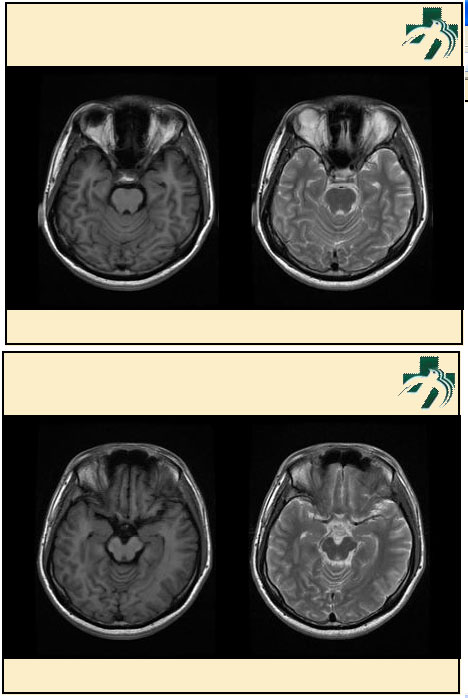

奴卡氏菌感染

第九期三博

读片会

病例之四

北京协和医院 提供

男性,22岁。自觉虫咬后皮疹、肢体麻木4月